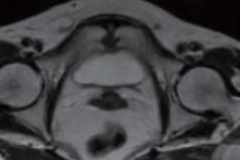

3.磁共振扫描(MRI)

影像学表现为:耻骨联合间隙可不同程度增宽,间隙内可见带状透亮间隙,单侧或双侧耻骨联合骨缘局限骨质硬化,少数囊变;耻骨联合骨缘锯齿状、鼠咬状、虫蚀状骨质破坏,边缘不光整,有时可见游离小骨块,早期骨质呈长T1长T2信号,晚期骨质均呈低信号。